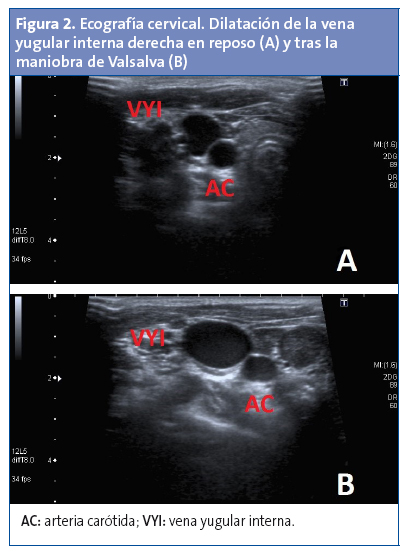

Durante la exploración física se evidencia una tumoración blanda, depresible, de 5 × 4,5 cm en el triángulo cervical anterior del lado derecho, que aparece con el esfuerzo, tos o maniobras de Valsalva y que desaparece en reposo (Fig. 1). En la palpación no hay aumento de temperatura local, la tumoración no es dolorosa, y la transiluminación es negativa. Se palpan microadenopatías latero-cervicales bilaterales. En la auscultación cervical no se ausculta soplos ni zumbidos. El examen físico general es normal. Se realiza una ecografía cervical, que muestra una tumoración anecoica, que corresponde a la vena yugular interna derecha, que aumenta de calibre respecto a la contralateral con maniobras de Valsalva (Fig. 2).

La ecografía durante la maniobra de Valsalva fácilmente establece el diagnóstico de flebectasia de la vena yugular y por tanto debería ser la primera prueba de imagen diagnóstica. Sin embargo, no existen datos en la literatura médica con respecto a los puntos de corte para las variables ecográficas que puedan discriminar entre una vena normal y flebectasia. Con el fin de establecer criterios diagnósticos ecográficos, Eksioglu encontró que el área de sección transversal (AST) de 220 mm2 de la vena yugular interna derecha durante la maniobra de Valsalva tenía una sensibilidad del 92,3% y una especificidad del 92%6; sin embargo, se necesitan más estudios para establecer el verdadero punto de corte. Recientemente se han descrito los valores ecográficos normales del diámetro de la vena yugular interna desde recién nacidos hasta los 18 años7. La ecografía Doppler color confirma la presencia o ausencia de flujo sanguíneo y la formación de trombo intraluminal, y es considerada el gold standard para el diagnóstico de flebectasia de la vena yugular8.